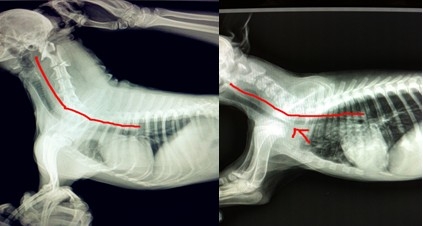

上面這兩張圖片來自于我院的兩張X光數碼片,第一張圖片是一根正常的氣管,第二張可以在尖頭所指的地方看見明顯的狹窄,由于此圖是手機翻拍,若為原圖,更加明顯,通過對比您可以清晰的發現區別和問題,所以及時就醫是非常積極的措施。